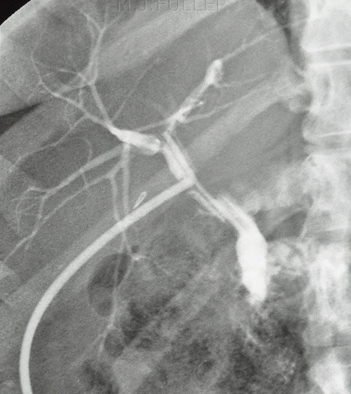

La

cholangio-pancreatographie retrograde par voie endoscopique

(ERCP): Methode invasive pour explore et

traitement de quelquesERCP affections de voie biliaire

: L'endoscopie est en place dans le tube digestif duodenum

D2 par la bouche et insertion un catheter en Teflon

avec guide (0.035) dans ampoule de Vater et guidee a canal

choledoque . Par cette voie on peu opacifie des voies

biliaires par contrast iodique ou de dilatation une portion stenosant de

voie biliaire par le Stent . Technique doit etre

realise sous anesthesie generale . Complication de cette

technique est : Pancreatite( 5% ) , hemorragie , perforation

et pneumoperitoine ou pneumoretroperitoine , ou infection de

voie biliaire ( cholangitis ) . Contre indication de cette

technique sont : deformation anatomie post -chirugical

, anormalie de l' oesophage , , estoma et duodenum , maladie

de coagulation du sang et sur le maladie a etat

instable

| |

|

Par voie endoscopie duodenal

on peu place une chatheter a guide a spinter Oddie

au canal cholodioque . Radioopaque iodique peu

injecte et control sous scopie ( amplificateur de

brillance ) . Cliche expose |

Image radiologique normale

une cholangio-pancreatico retrograde par voie

endoscopique ( ERCP ) . Voies biliaires principale

intra et extrahepatique et canal de Wirsung sont en

voyaient . |